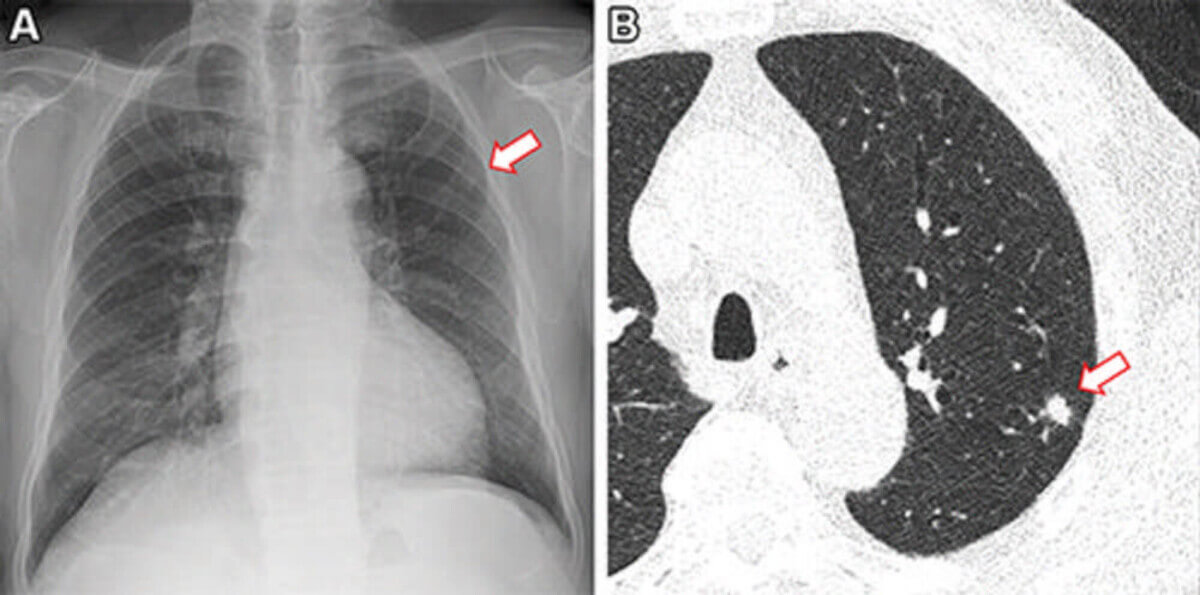

Images in a 73-year-old man who underwent chest radiography and low-dose CT for health checkup purposes and was allocated to the non–artificial intelligence (AI) group. (A) Frontal chest radiograph shows a small nodular opacity (arrow) in the left upper lung zone, which was missed by the designated reporting radiologist. (B) Axial, noncontrast, low-dose chest CT scan shows a 9-mm solid nodule (arrow) in the left upper lobe. The nodule showed low metabolism at PET and decreased in size at follow-up CT. It was confirmed to be an inflammatory nodule. (CREDIT: Radiological Society of North America)